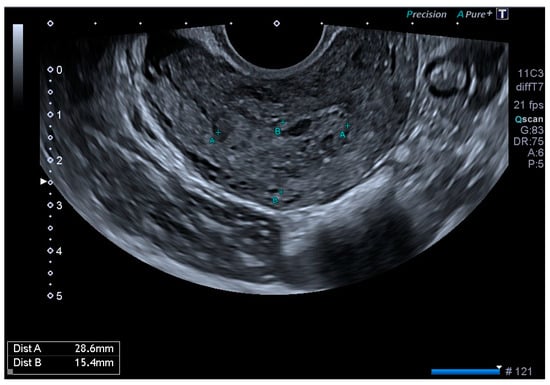

CT angiography showed a complex network of millimetre-sized vessels of tortuous appearance with rapid contrast enhancement in the late arterial phase and isodensity in the portal phase (similar to systemic venous vessels). This network extended through the right parametrium, through the myometrial fundus, and apparently into the endometrium (Figure 3 and Figure 4). The radiological findings were compatible with a uterine arteriovenous malformation.

Figure 3. Cross-sectional pelvic CT angiography.